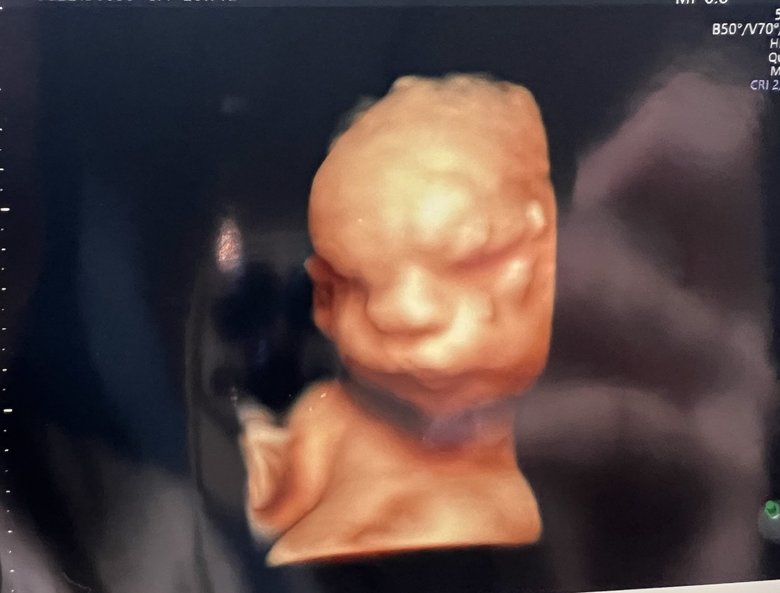

異常発覚後、妊娠24週(妊娠7か月)のころのエコー画像

7/28